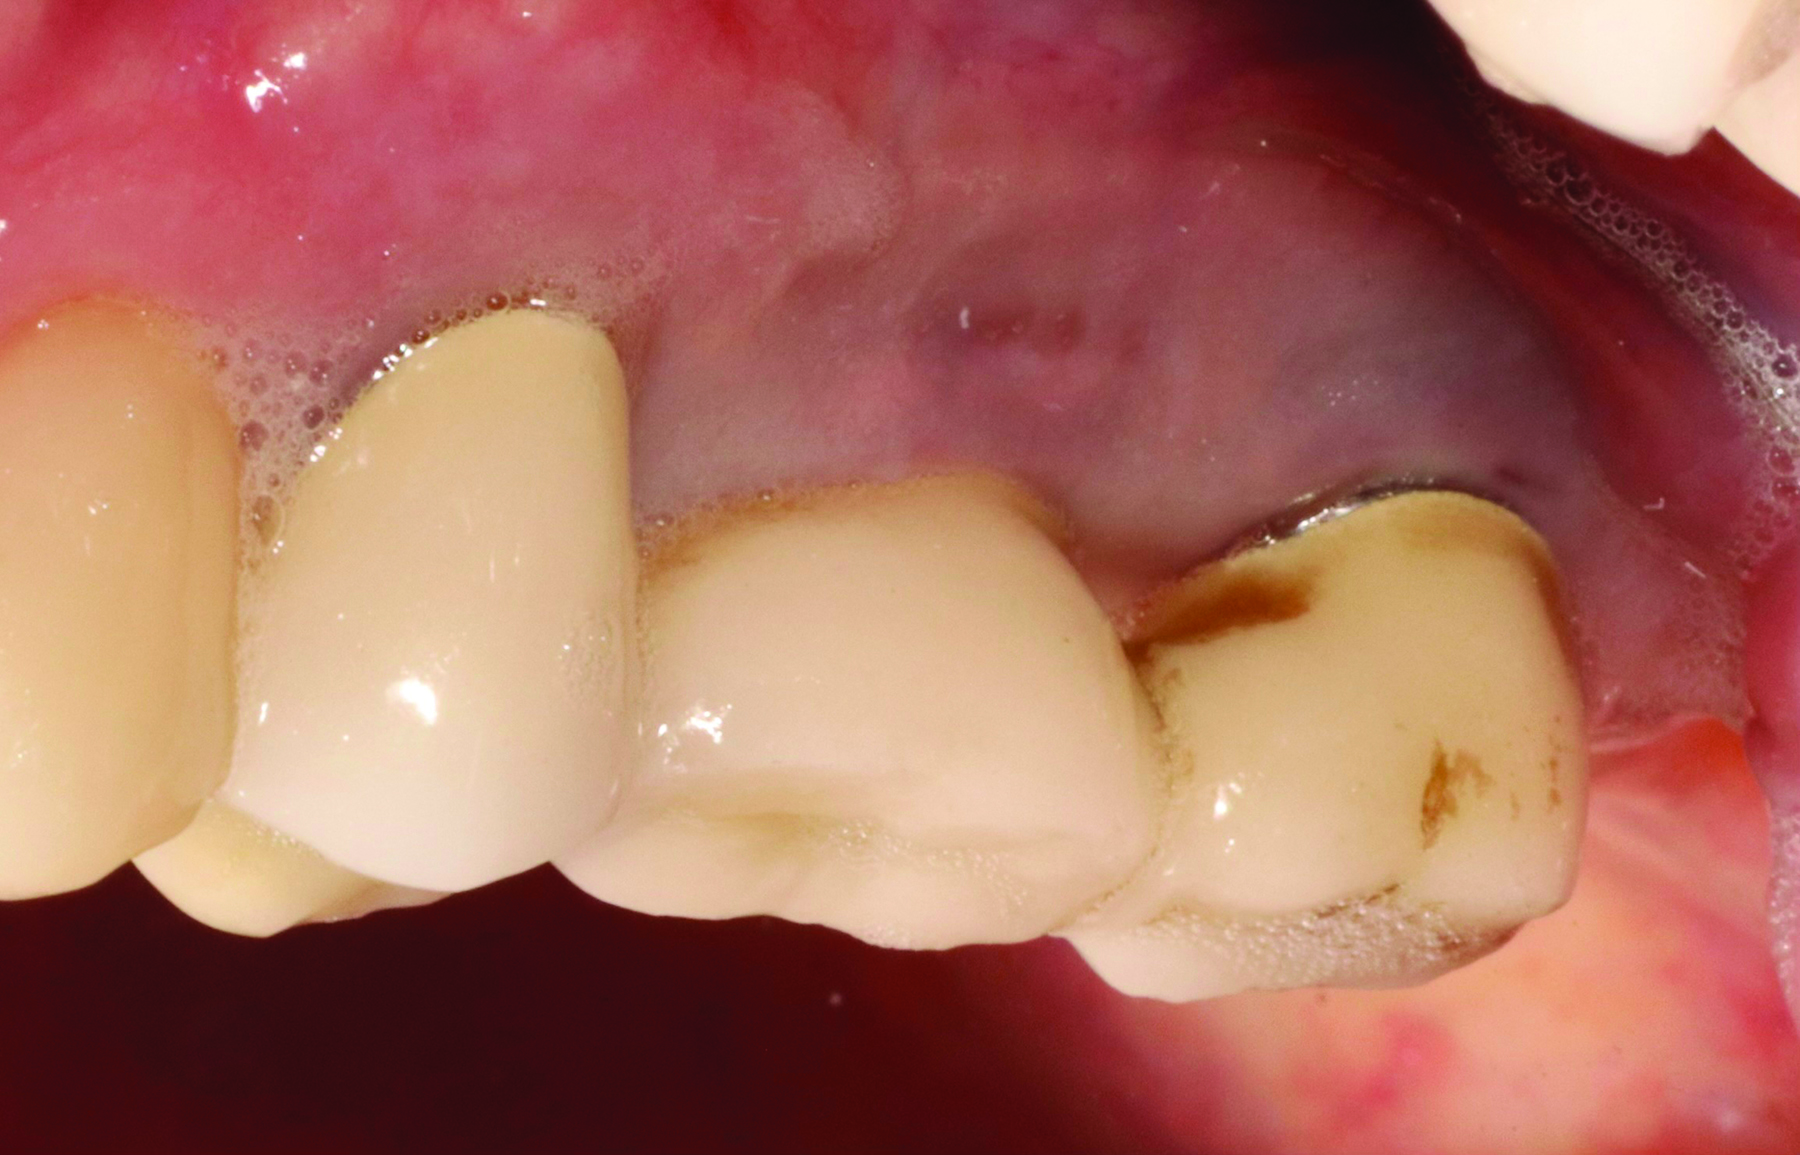

Fig 3 and Fig 4. Pre- (Fig 3) and post-treatment (Fig 4) photographs of a patient who received free gingival grafting at implant sites Nos. 21 and 22. Note the increased amount of keratinized tissue at the areas postoperatively (Fig 4). The patient was placed on 3-month supportive peri-implant care post-surgery and reported increased comfort during her home care regimen.

Figure 3